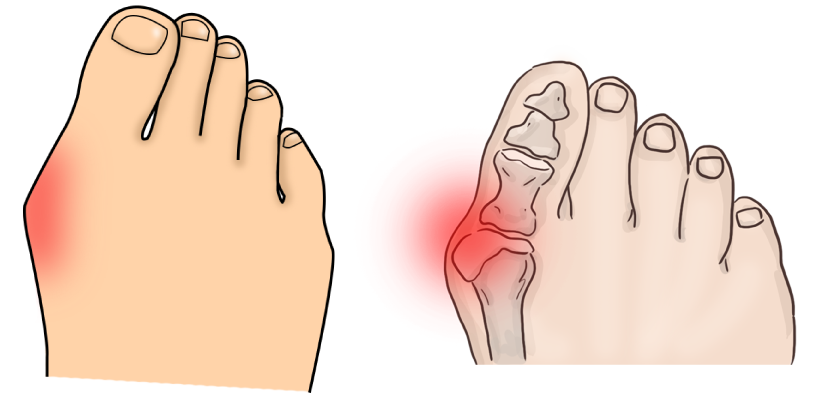

무지외반증 진행과정

소건막류 진행과정